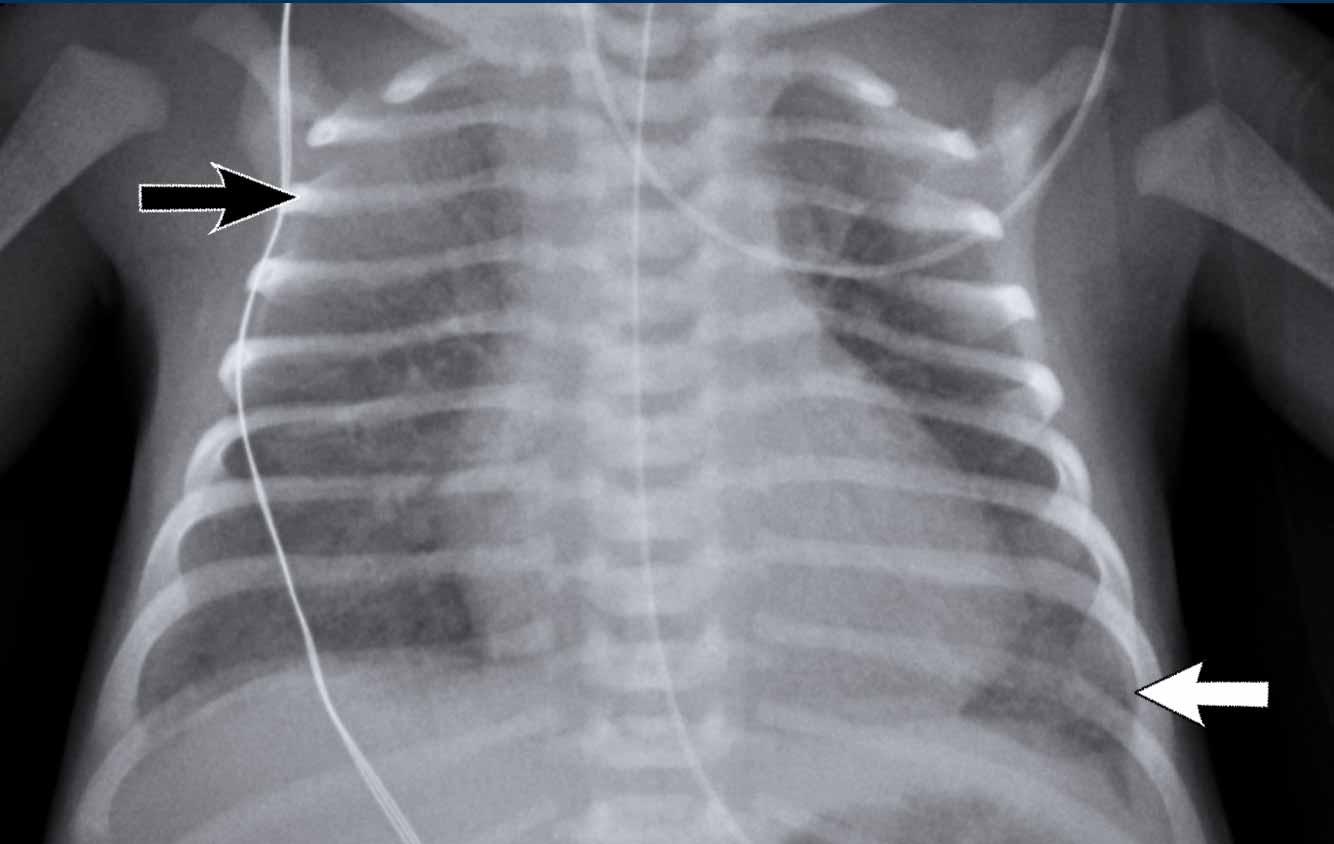

Trẻ sơ sinh 32 tuần tuổi thai. Đang được điều trị suy hô hấp cấp (RDS) bằng CPAP, xuất hiện suy hô hấp đột ngột.

First study the image.

What are the findings?

Hình ảnh

Có tràn khí màng phổi bên phải.

Các cấu trúc đường giữa bị đẩy lệch sang trái.

Phổi trái cho thấy hình ảnh lưới nốt phù hợp với hội chứng suy hô hấp (RDS).

Phổi phải không xẹp hoàn toàn do độ cứng của nhu mô trong hội chứng suy hô hấp (RDS) và dịch.